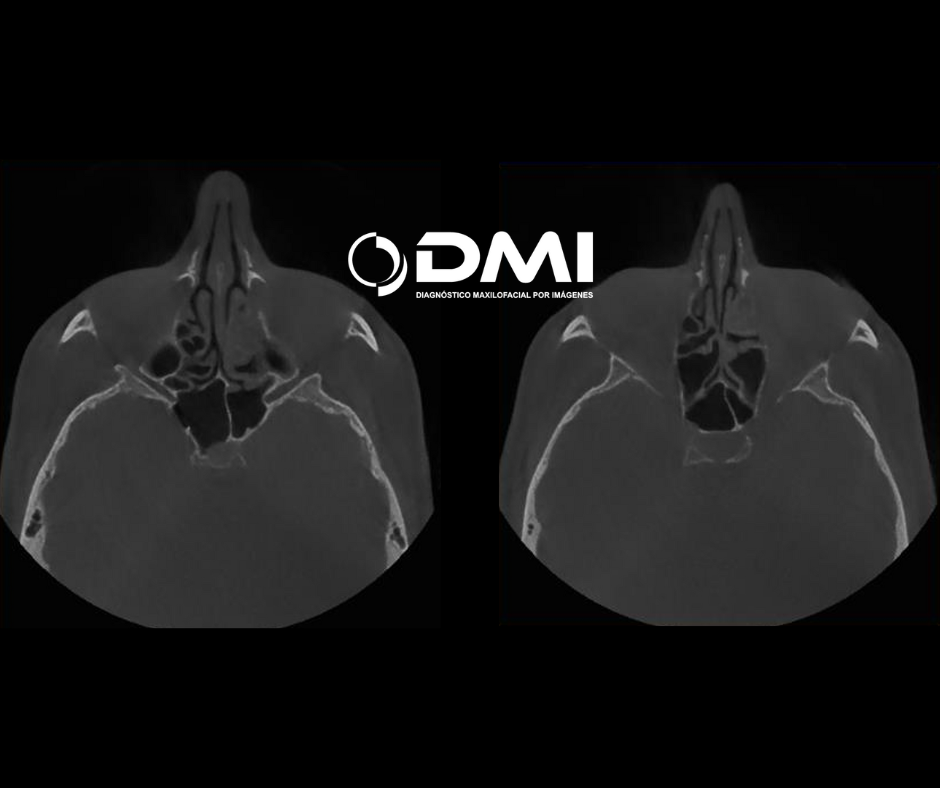

cortes axiales en un barrido desde inferior a superior se evidencia senos paranasales conservados en apariencia,

sus corticales óseas tienen densidad tomográfica homogénea, sin lesiones

líticas, ni osteogénicas, en contraste el seno maxilar derecho con presencia de engrosamiento de la mucosa antral.

El seno maxilar izquierdo ocupado de contenido isodenso.

Cortes axiales que evidencian meatos inferiores con contenido isodenso, seno maxilar derecho sin contenido isodenso, El seno maxilar izquierdo ocupado casi en su totalidad por contenido isodenso.